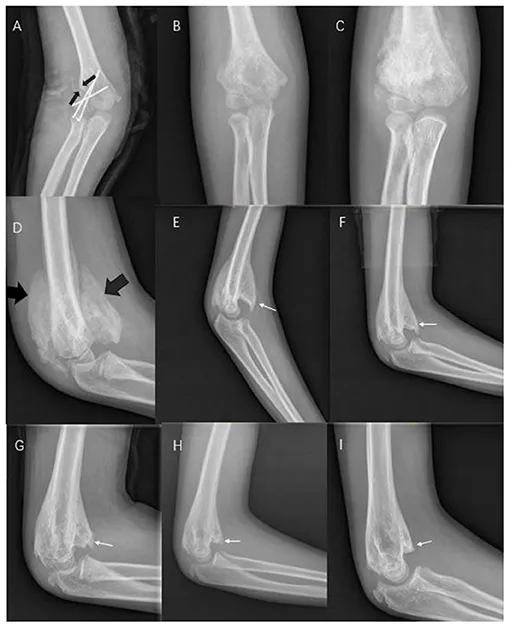

- Myositis Ossificans:

- Patho: Post-traumatic heterotopic ossification in muscle.

- Sites: Quadriceps, brachialis. Clinically: Pain, swelling, ↓ROM.

- X-ray: Fluffy calcification → mature peripheral ossification.

- Mgmt: Rest, NSAIDs. ⚠️ AVOID early aggressive massage/surgery.